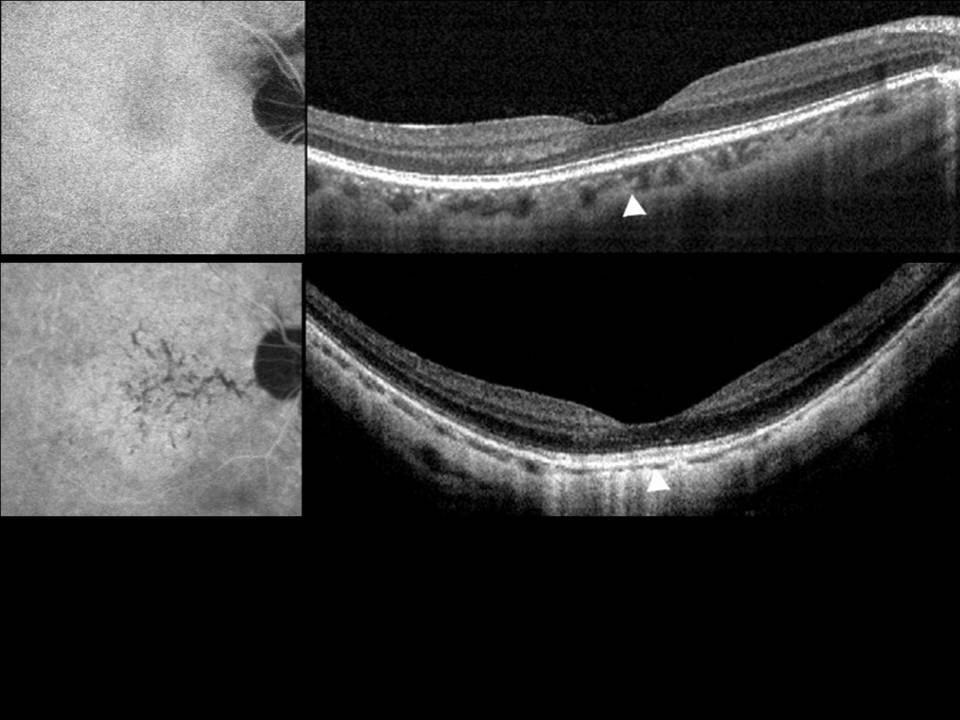

A miopia patológica é uma causa importante de cegueira, com prevalência crescente nos países desenvolvidos e em idades progressivamente mais jovens. É-lhe tradicionalmente atribuída uma forte componente genética, reconhecendo-se hoje fatores ambientais que podem limitar a sua progressão. Embora em muitos casos o agravamento da acuidade visual fosse atribuído à presença de neovascularização coroideia, descolamento de retina ou desenvolvimento de buraco macular, noutros esta progressão permanece por explicar. Novas técnicas de tomografia por coerência óptica permitiram recentemente a descoberta de entidades patológicas relacionadas com a maculopatia miópica, que abrem portas ao avanço na compreensão fisiopatológica da doença e na sua abordagem terapêutica, particularmente cirúrgica. Salientam-se os fenómenos de foveosquisis miópica, cavitação intracoroideia, tração vítrea paravascular (com formação de quistos, micropregas e defeitos lamelares) e fenómenos de distorção macular que revemos neste trabalho.